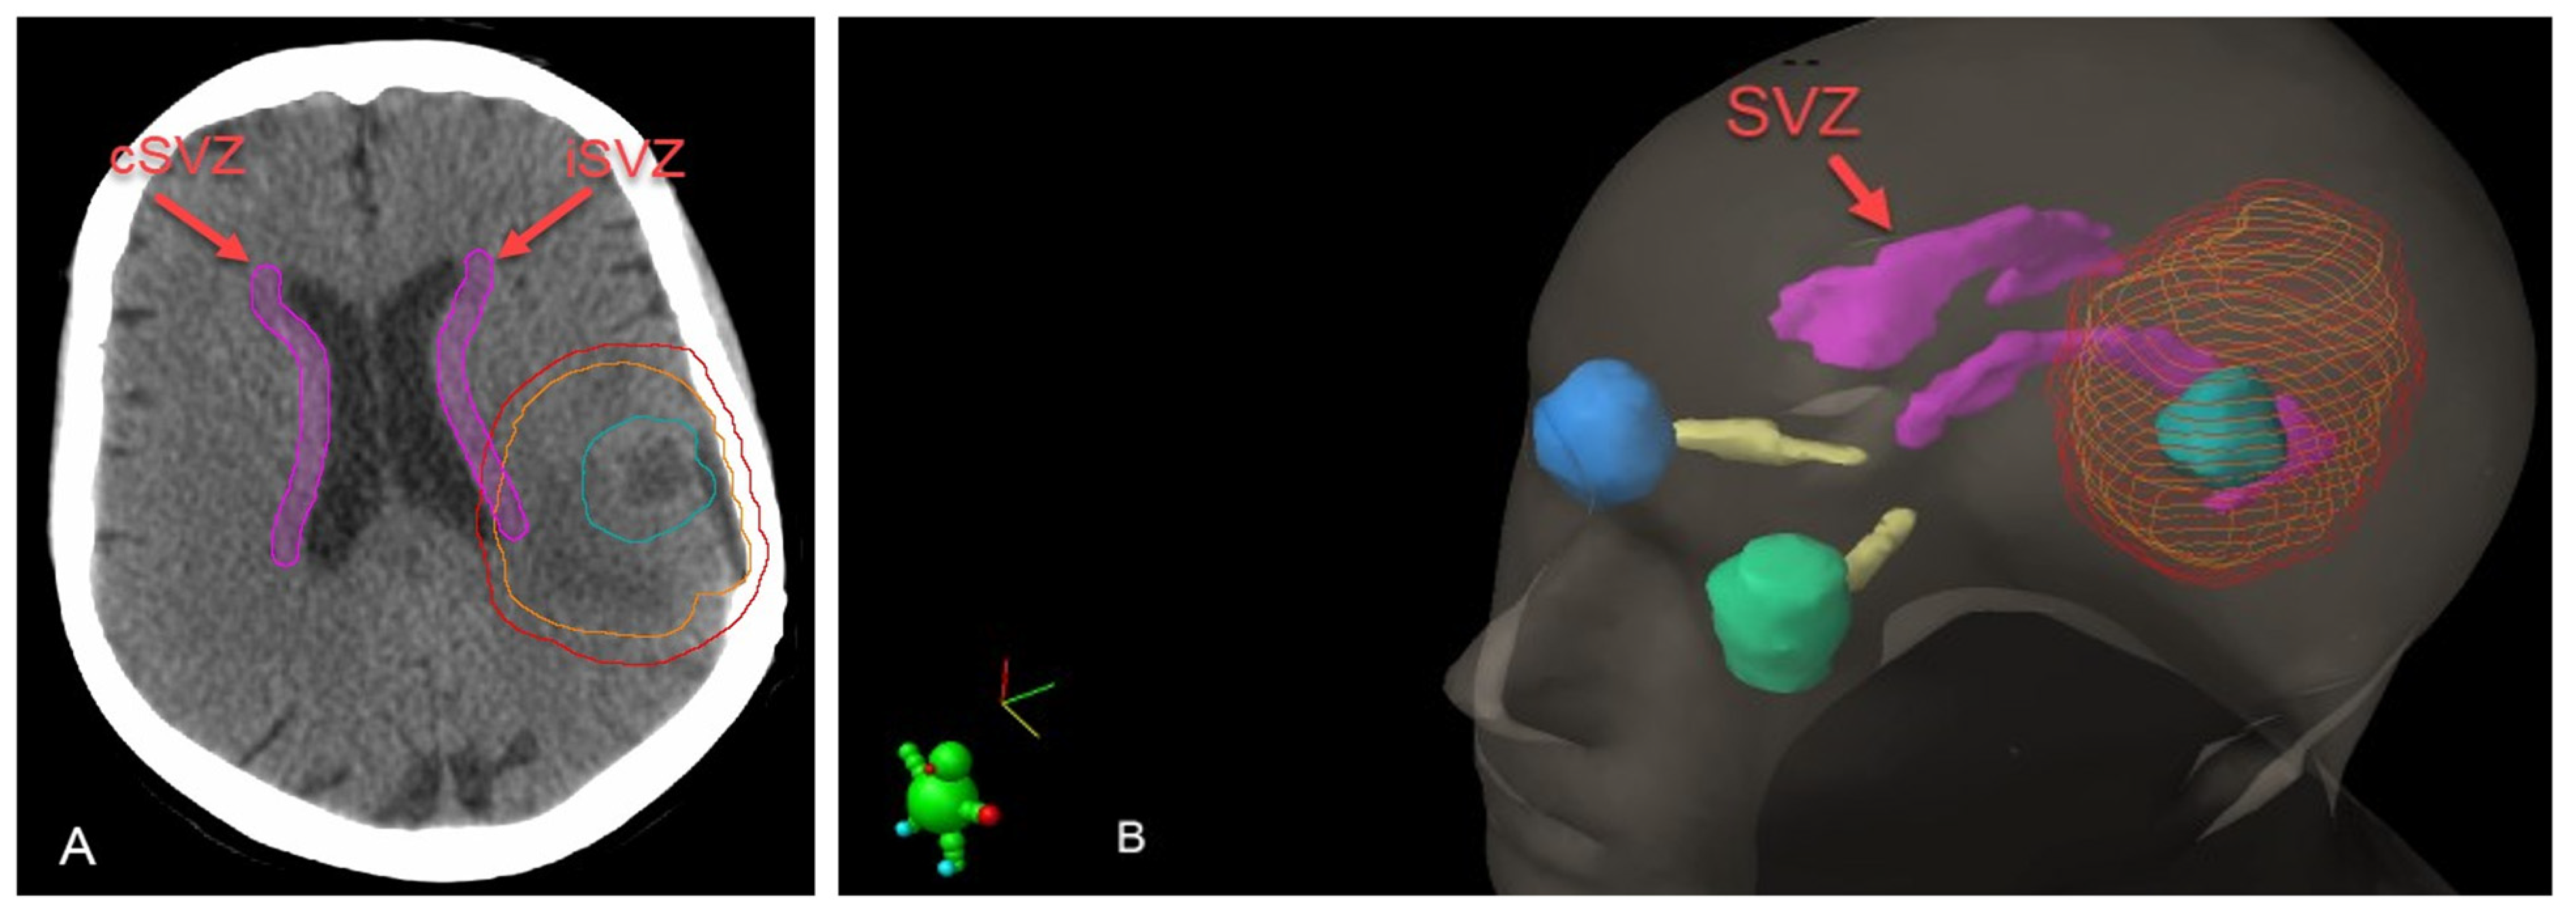

2.3. SVZ MRI Characteristics, Delineation and Dosimetric Data